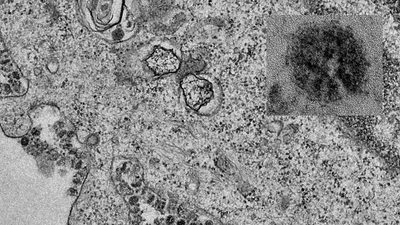

(PLO)- Báo South China Morning Post (SCMP) dẫn số liệu từ Ủy ban Y tế Quốc gia Trung Quốc (NHC) cho biết tính tới 18 giờ 37 phút ngày 11-2, trên thế giới có tổng cộng 1.018 người tử vong vì dịch viêm đường hô hấp cấp do chủng mới của virus Corona (2019-nCoV) gây ra, gọi tắt là dịch Corona, và 43.112 ca nhiễm.